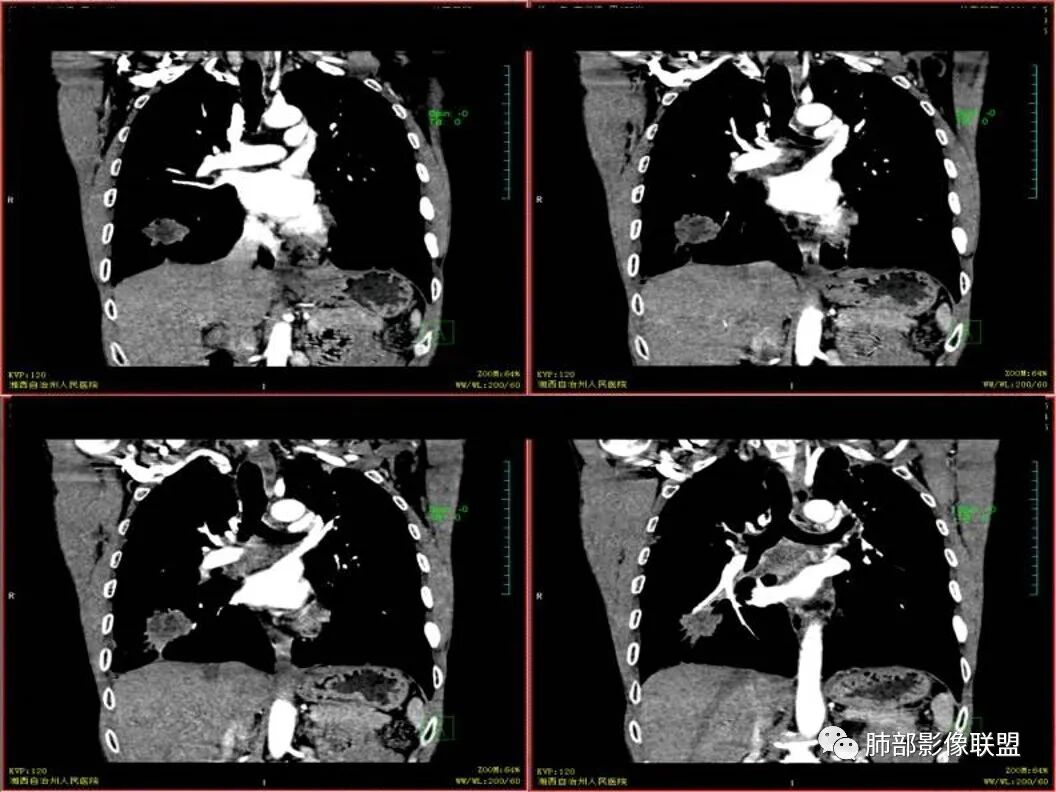

双上肺多发病灶,考虑结核(陈旧灶为主),右肺下叶前基底段占位,分叶、毛刺、胸膜牵拉,中央坏死,局部壁不光滑,前基底段支气管未见显示,不均匀强化,病灶远端阻塞性炎症,纵隔淋巴结肿大、融合。综合考虑恶性病变,鳞癌可能大。

临床 中年男性,咳嗽盗汗、老结核史,血沉高、t试验阳性,结核应该存在,cyf高4倍,价值怎么样待验证。影像 :两上肺实变加粗大索条灶,两肺野弥漫粟粒,考虑结核应该问题不大。重点分析右下病灶:隆突下淋巴结肿大,但伴钙化,有边缘强化?淋巴结融合又是恶性征像?右下肺病灶冠状位总体方正,横断位总体三角型,长毛刺、近端也有渗出、坏死彻底、空洞壁光滑锐利,似有边缘强化?看做薄壁空洞?以上符合炎性病灶。   支持恶性的征像 :冠状位的空洞似有壁结节,偏心坏死。   综合 ,右下肺鳞癌(偏心空洞+cfy)+两肺结核。

老年男性,既往有肺结核病史。影像双上肺病灶考虑陈旧性肺结核病灶,关键是右下肺团块影,从视频看,右下叶前段分支有堵塞,病灶局部膨隆,有分叶,周围有磨玻璃,但边界不大清楚,远端还有可以阻塞性炎征象,内部有偏远心端坏死,故考虑恶性可能性大。

影像表现为 双肺上叶多发索条斑片影,可见支气管牵拉性扩张,考虑为陈旧肺结核纤维硬结灶。右肺下叶前基底段团块影膨隆生长,边界不清,呈分叶,毛刺,胸膜牵拉,支气管截断,中央区坏死明显,但未形成空洞,坏死区边缘光整,不均匀环形强化,隐约见壁结节。纵隔淋巴结肿大伴钙化,病灶远端见阻塞性炎症,结合CYFRA21-1偏高,应想到考虑恶性病变,鳞癌可能性大。